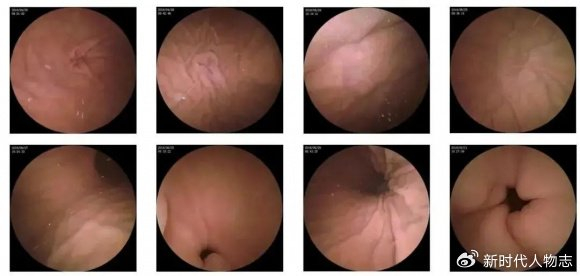

肛門息肉早期圖片及其相關介紹,肛門息肉早期圖片與詳細介紹

摘要:本文介紹了肛門息肉早期的圖片和相關介紹。肛門息肉是肛門部位的一種常見病變,早期發(fā)現(xiàn)對于治療具有重要意義。文章通過圖片展示了肛門息肉的早期形態(tài),并簡要介紹了其癥狀、原因、診斷和治療等方面的信息,以幫助人們更好地了...